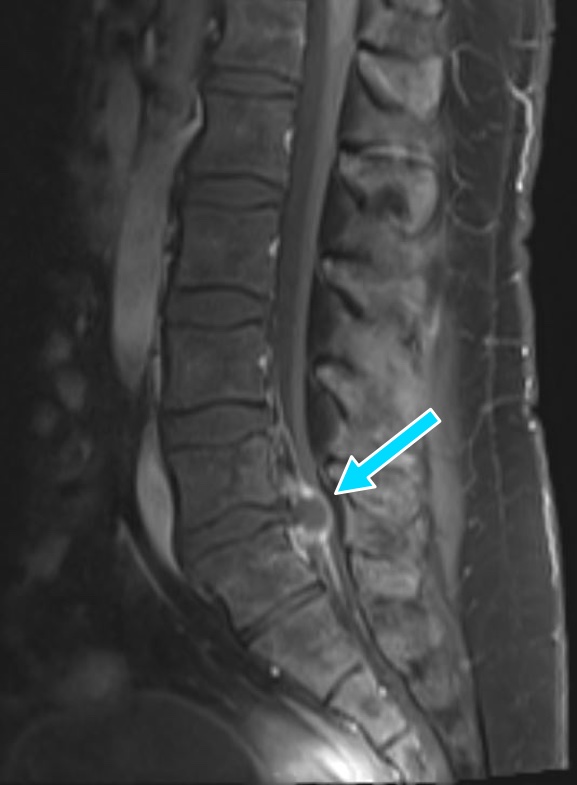

A 37 yo male with chronic low back pain presents with acutely worsening low back pain and ambulatory dysfunction. Patient reports being unable to walk due to severity of back pain over the last 2-3 days. Denies any red flag symptoms such as saddle anesthesia, fevers, cancer history, bowel or bladder incontinence, or IV drug use. Further history and physical exam are difficult to obtain due to the patient's significant discomfort and unwillingness to participate. Lumbar spine MRI shown below. What's the diagnosis? Scroll down for answer.

Answer: L5/S1 disc herniation

Radiology read of MRI:

1. Large peripherally enhancing left posterior paracentral structure at L5-S1 compressing

the descending left S1 nerve root and severely compressing the spinal canal and cauda equina nerve roots. This most likely represents a large disc extrusion rather

than an abscess.

2. Epidural lipomatosis congenitally narrowing the lumbar spinal canal, particularly at L5-S1, nearly completely effacing the sacral spinal canal.